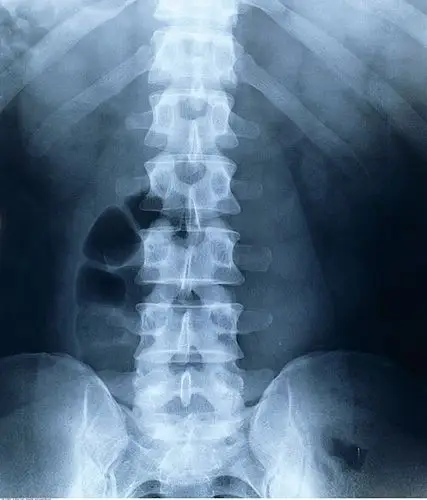

x光,脊椎